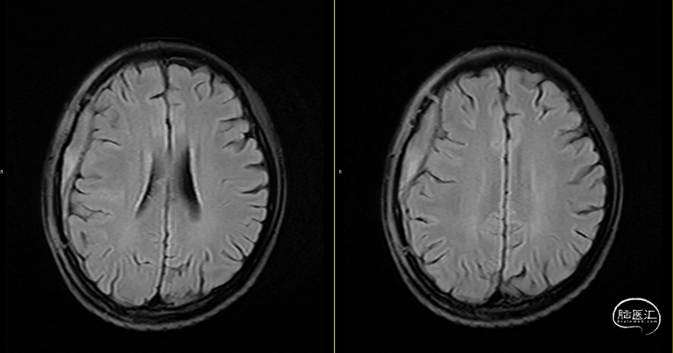

第2次术后12天,仍有间断头痛,刀口愈合可,复查颅脑MRI(如上图):右侧额顶颞部软组织稍增厚,右侧额顶部颅板下见条片状长T1、长T2信号,T2FLAIR呈稍高信号,边界清,DWI(b=1000)呈混杂高信号,相应ADC呈混杂高信号影,加用美罗培南联合万古霉素抗炎治疗。